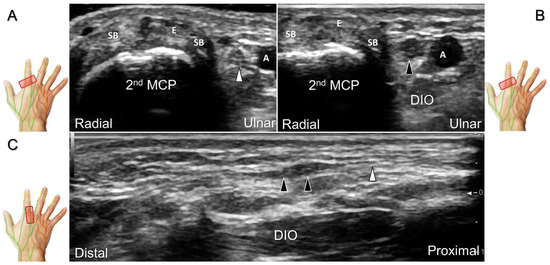

Figure 33. Sonographic imaging of the dorsal common digital nerve on the metacarpal bone (A), toward the metacarpal head (B). Dorsal proper digital nerves on the proximal phalanx (C), and the terminal nerve originating from the palmar proper digital nerve on the distal phalanx of third finger (D). Arrowheads: dorsal common digital nerve; arrows: palmar proper digital nerve. MCP: metacarpal bone; SB: sagittal band; E: extensor tendon; Cs: central slip; PP: proximal phalanx; T: terminal band; DP: distal phalanx; DIO, dorsal interosseous muscle.

Scanning Technique

The transducer is positioned on the axial plane of the dorsal metacarpal joint in the target digit. The dorsal proper digital nerves can be found on either side of the sagittal band (Figure 33A). The transducer is moved proximally and the dorsal common digital nerves can be observed superficial to the extensor (usually the extensor digitorum proprius) tendons (Figure 33B). By returning to the level of the sagittal band and moving the transducer distally, the dorsal proper digital nerves can be seen superficial to and alongside the central slip of the finger extensor tendon (Figure 33C). Alternatively, moving the transducer distally toward the proximal phalanx of the first to the radial aspect of the fourth phalanx allows observation of the nerve fascicles of the palmar proper digital nerve originating from the median nerve (Figure 33D).

Clinical Implication

Injuries to the dorsal common digital nerve typically occur in the workplace as a result of cutting or crushing. However, the nerve can also sustain damage due to various other factors such as fracture, ganglia, tenosynovitis, tumor (Figure 34), foreign objects, or boxing, which may cause contusion over the first knuckles (Figure 35).